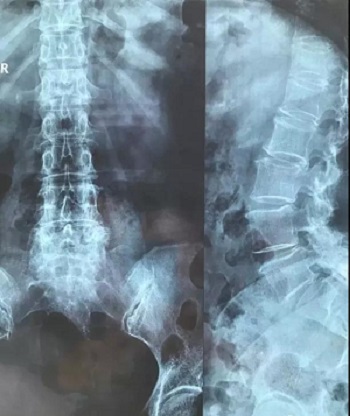

八、拍片子时,如果一张片子上有两张图像的时候,合起来拍一张,分开再各拍一张(如以下三张)